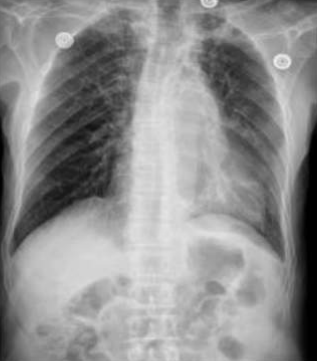

âȘ Table 5: We visualize samples of the generated reports for three cases. We bold the identical descriptions, underline the additional identified findings, and in red the failure findings..

X-ray Image | Baseline | M2TR | R2Gen | Ours |

![]() |

RĂ©gression du pneumothorax droit./Drain en place au niveau apical droit./OpacitĂ© en bande linĂ©aire au niveau du tiers infĂ©rieure de lâhĂ©michamp pulmonaire gauche./Scissurite droite./Silhouette cardiaque dâaspect normal./Absence dâanomalie du gril costal./ | StabilitĂ© du pneumothorax droit./Drain apical droit en place et fonctionnel./Bande opacifiante au niveau du tiers moyen de lâhĂ©michamp pulmonaire gauche./LĂ©gĂšre scissurite droite./ | Diminution du Pneumothorax gauche./Drain thoracique positionnĂ© Ă l'apex gauche./OpacitĂ© linĂ©aire sur le tiers supĂ©rieur de l'hĂ©michamp pulmonaire droit./ | RĂ©gression marquĂ©e du pneumothorax droit./Disposition dâun drain au niveau apical gauche./OpacitĂ© linĂ©aire dans le tiers infĂ©rieur de lâhĂ©michamp pulmonaire gauche./NormalitĂ© du gril costal et des parties molles./ |